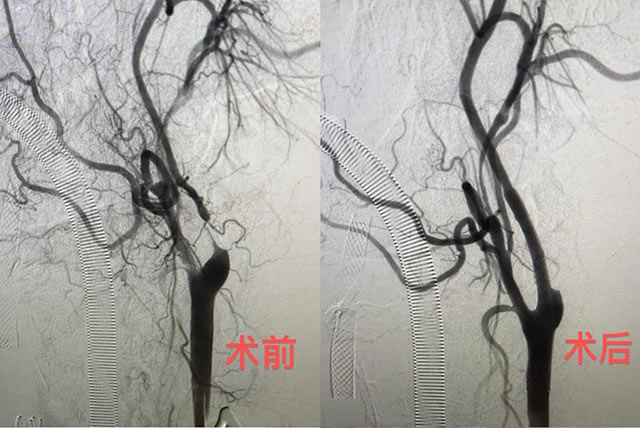

陈光忠团队为其实施了华南首例颈动脉狭窄治疗新技术——经颈动脉血运重建术(TCAR)。手术直接在颈动脉上穿刺,阻断血流约20分钟,再进行球囊扩张与支架植入。“最关键的操作是进行了血流逆向保护”,陈光忠说,就像开个外挂一样,在体外接驳一条人工血管,从颈动脉接到股静脉,里面有一个特别密的保护网,能兜住绝大部分脱落的斑块栓子,“这样我们在放球囊扩张血管时,就不用太担心血栓脱落流到脑血管里。”该术式海外临床数据显示,术后30天患者卒中事件的发生率为1.4%,比颈动脉支架成形术(CAS)减少了约3.6%。手术不经过主动脉弓,避开了颅神经损伤,降低了脑梗、心梗的发生风险,让颈动脉狭窄的治疗更安全、更有效。